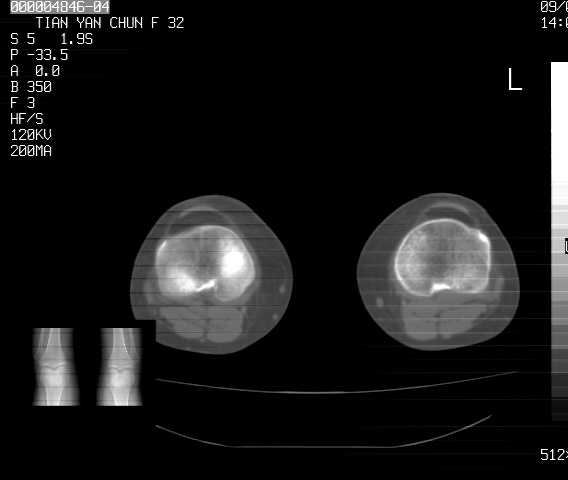

标题: CT18487:请会诊,女32岁,左膝疼痛数日 [打印本页]

标题: CT18487:请会诊,女32岁,左膝疼痛数日

关节面软骨有硬化环考虑退行性变

定位片可见髁间棘骨质增生,支持膝关节退行性变。

定位片可见髁间棘骨质增生,支持膝关节退行性变。建议mri 检查

考虑骨性关节炎